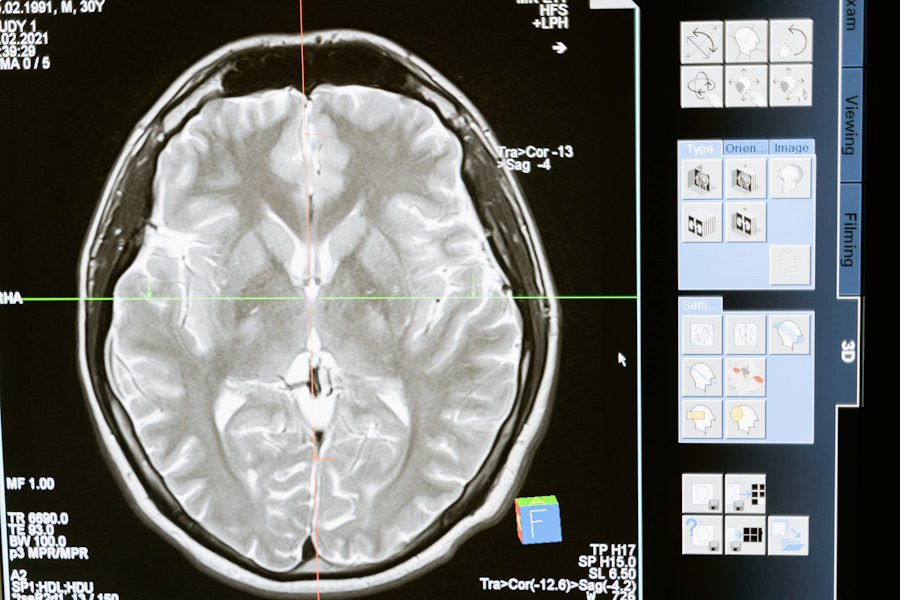

Исследователи University of Stanford (США) разработали модель ИИ (искусственного интеллекта), с достоверностью > 90% определяющую пол человека на основе МРТ его мозга. Этот прорыв бросает вызов давним спорам о существовании значительных половых различий в организации мозга, сообщает Neuroscience News (NN).

Модель искусственного интеллекта была сфокусирована на анализе динамических данных магнитно-резонансной томографии (МРТ), выявляя определенные сети мозга, такие как режим по умолчанию, полосатое тело и лимбические сети. Эти области оказались решающими для различения мужского и женского мозга.